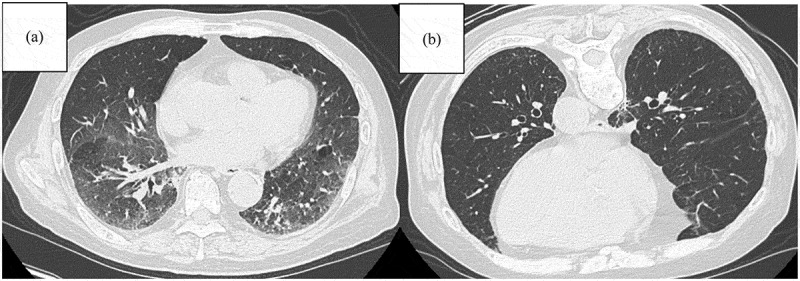

免疫疗法彻底改变了非小细胞肺癌(NSCLC)的治疗前景,显著提高了患者的生存结果,并为患者带来了新的希望。然而,NSCLC患者间质性肺异常(ILAs)的存在带来了独特的挑战,特别是由于免疫检查点抑制剂(ICI)相关肺炎的风险升高,这可能导致治疗中断并对预后产生不利影响。通常在计算机断层扫描成像中偶然发现的ILAs与间质性肺疾病进展的风险增加有关,并且已被确定为接受免疫治疗的非小细胞肺癌患者临床预后不良的潜在预测因子。这篇综述综述了目前对ILAs和ICI治疗之间相互作用的理解,讨论了患病率、放射学特征、风险分层和管理策略。此外,它强调需要前瞻性、多中心研究来建立具有ILAs的非小细胞肺癌患者的最佳治疗方式,以确保更安全、更有效的免疫治疗。

Immunotherapy has revolutionized the treatment landscape of non-small cell lung cancer (NSCLC), significantly improving survival outcomes and offering renewed hope to patients. However, the presence of interstitial lung abnormalities (ILAs) in patients with NSCLC presents unique challenges, especially due to the elevated risk of immune checkpoint inhibitor (ICI)-related pneumonitis, which can result in treatment interruptions and adversely affect prognosis. ILAs, often detected incidentally on computed tomography imaging, are associated with an increased risk of progression to interstitial lung disease and have been identified as a potential predictor of poor clinical outcomes in patients with NSCLC receiving immunotherapy. This review offers an overview of the current understanding of the interaction between ILAs and ICI therapy, discussing prevalence, radiological features, risk stratification, and management strategies. Additionally, it highlights the need for prospective, multicenter studies to establish optimal treatment modalities for patients with NSCLC having ILAs, to ensure safer and more effective immunotherapy.